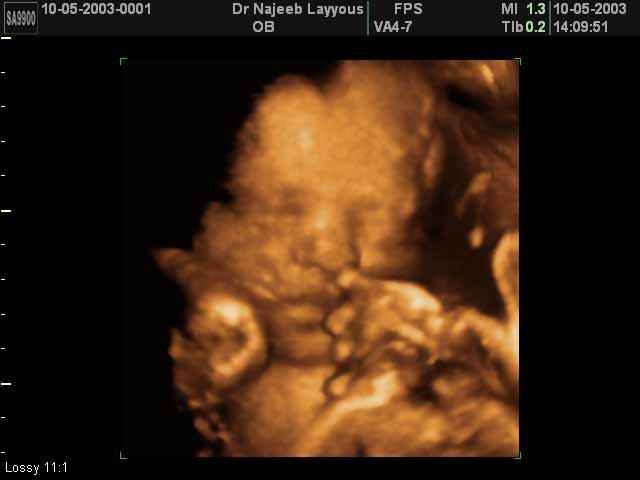

- Fetal Face Ultrasound Photos

- 3D Fetal Profile Ultrasound Scan Photos

- The Clinical Advantages of 3D and 4D Ultrasound

- Definition and Features of Four Dimensional Ultrasound

- Uses of 4D Ultrasound scan

- The importance of 4D ultrasound imaging in pregnancy